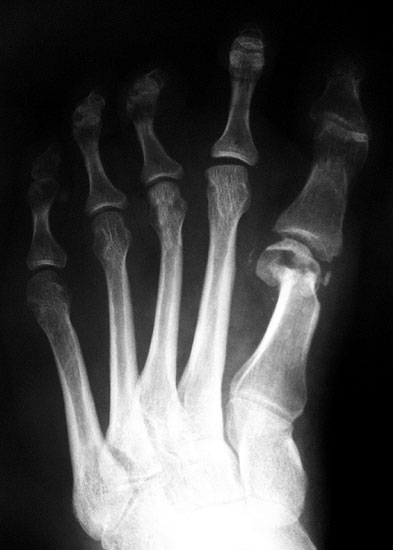

Ein Hallux valgus interphalangeus hat neben dem optischen Effekt der „nicht geraden Großzehe“ zur Folge, dass Extensor- und Flexor hallucis longus Sehne lateral des Drehpunktes des Großzehengrundgelenks verlaufen 11. Die Kräfte in Richtung Valgus sind erhöht (Abbildung 5). Darüber hinaus scheint ein Hallux valgus interphalangeus einen negativen Effekt auf den Bewegungsumfang im Großzehengrundgelenk zu haben 12. Die Akin Osteotomie bietet bei isoliertem Hallux valgus interphalangeus eine gute Möglichkeit die Stellung der Großzehe zu verbessern (Abbildung 6).